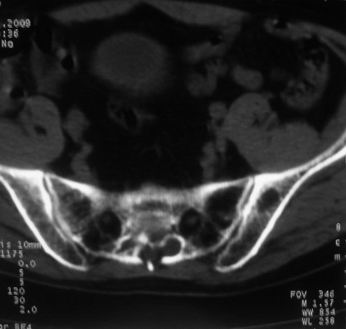

男,85岁,排尿困难。骶椎有问题吗?

前列腺明显增大,突入膀胱,各叶比例协调,密度均匀,精囊腺及精囊角正常;考虑良性增大。

骶骨没有看到明显异常。

1)考虑前列腺增生症并阻塞性膀胱炎。2)骶椎右侧类似囊状骨质密度减低区,边缘骨质硬化,其内为软组织密度影填塞,相邻之骶椎椎管受压变形;考虑为骶椎右侧囊肿或神经纤维瘤。

1)前列腺明显增大,突入膀胱,各叶比例协调,密度均匀,精囊腺及精囊角正常;考虑前列腺增生症并阻塞性膀胱炎。2)骶椎右侧类似囊状骨质密度减低区,边缘骨质硬化,其内为软组织密度影填塞,相邻之骶椎椎管受压变形;考虑为骶椎右侧囊肿或神经纤维瘤。

建议:行mri检查。